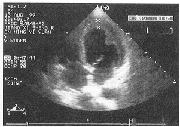

超声诊断嗜酸性细胞心内膜病1例

叶雪存 冯莉莉 付明伟

330006 江西省人民医院超声科

患者男性 ......